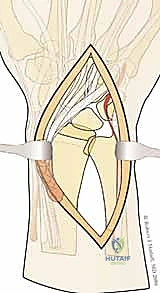

1. المداخل الجراحية (Surgical Approaches)

نظراً لأن الكسر يتم تثبيته من جهات متعددة، قد يستخدم الدكتور هطيف شقوقاً جراحية صغيرة ومدروسة بدلاً من شق واحد كبير.

* المدخل الأمامي (Volar Approach): للوصول إلى الحافة الهلالية والسطح الأمامي لعظم الكعبرة. يتم إبعاد الأوتار والأعصاب (مثل العصب المتوسط) بعناية فائقة.

* المدخل الظهري أو الجانبي (Dorsal/Radial Approaches): شقوق صغيرة إضافية للوصول إلى شظية العمود الكعبري أو الجدار الظهري، مع الحفاظ التام على الأوتار الباسطة.